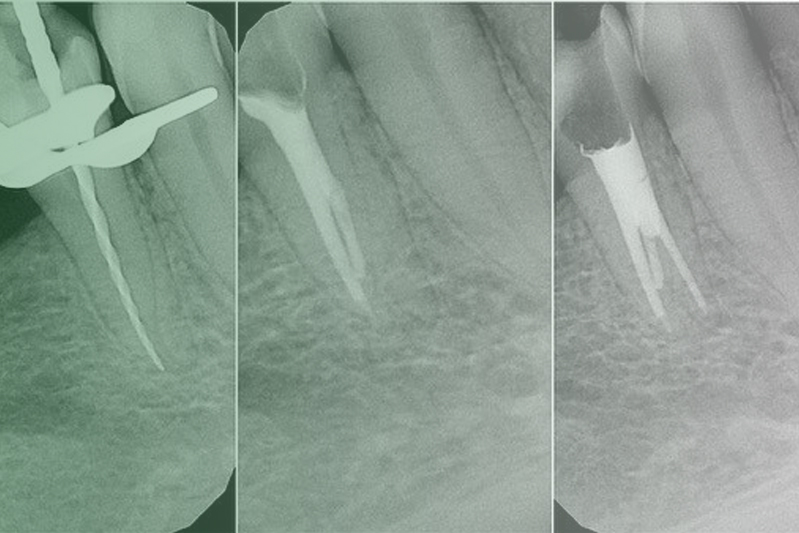

Клинический случай. Эндодонтия

Клинический случай